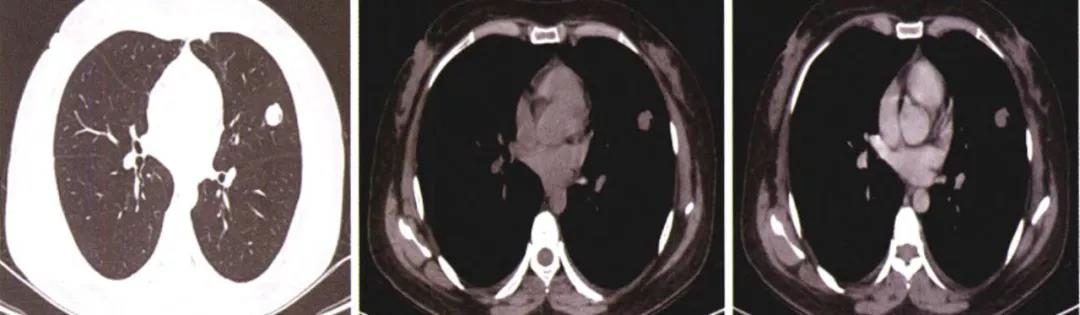

肺炎性假瘤多单发,呈类圆形或不规则形,呈磨玻璃样密度结节,边界多清楚、光滑,少数见浅分叶及粗长毛刺,可见「桃尖征」(图 5),是炎性假瘤包膜的黏连牵拉,可视为特征性表现。

病灶内可见较小薄壁空洞,边缘点状钙化,瘤周可见不规则条索影,近胸膜缘粘连可见「尖角征」,不与胸膜粘连缘平直,在病灶中间某一层面呈一侧边缘平直的刀切样变(图 6),或基于胸膜的方形征,具有较高特异性